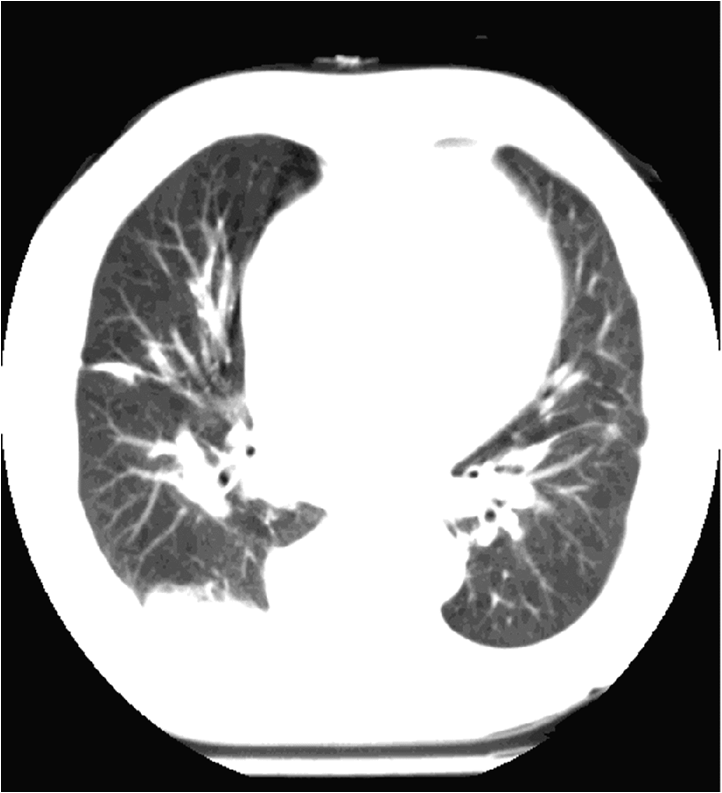

The brightness of the picture can also be altered, making too dark or too light parts of the picture assessable. The windowing allows changing of the brightness and contrast at the same time. If we change them accordingly tissues with different absorption can be highlighted. For example, low brightness and low contrast settings allows good visualization of the bone structures, but other tissues appear moderately pale. High brightness and contrast settings results in a good visualization of the lung tissue while other tissues appear bright and pale.

Figure 3.: The same CT image with soft tissue window (a) and lung window (b)